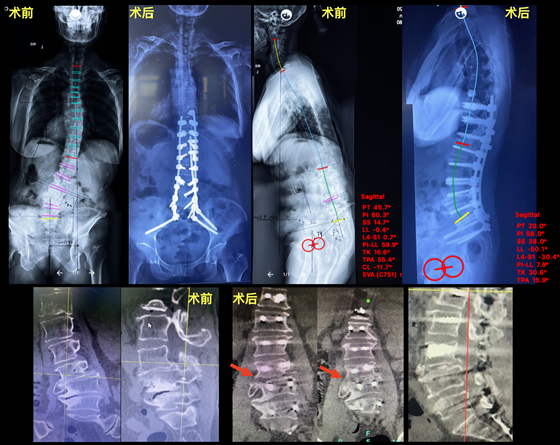

入院后,骨科陈芳田主任医师立即对余女士进行了详细体查,考虑是脊柱疾病导致余女士腰、腿疼痛问题,再结合影像学资料,发现余女士本该是一条笔直的脊柱却发生了侧弯,冠状面和矢状面都已严重失衡,并且第三、四节腰椎还出现了滑脱、侧方移位和畸形融合症状,同时余女士还患有严重的骨质疏松症。经过全面评估,最终患者被确诊为“成人退行性脊柱畸形;冠状面、矢状面失代偿;腰椎滑脱并侧方移位;腰椎管狭窄症;重度骨质疏松症”。

2022年7月24日,手术由王孝宾副教授主刀,在我院骨科陈芳田主任及其团队配合下,历时8个小时,成功为患者实施脊柱侧凸畸形截骨矫形手术。王孝宾副教授凭借精湛的技术,用骨刀经腰3-4椎间隙进行截骨,将原本已经融合的椎间隙重新打开,徒手置入19枚椎弓根螺钉、2枚S2AI螺钉和1枚mILS螺钉,并使用序贯矫形和卫星棒技术,最终将侧方滑移和前后滑脱的腰3-4椎体完全复位,并且完美矫正了脊柱冠状面和矢状面畸形状况。

术后,在我院骨科医护团队的精心治疗和护理下,余女士顺利康复,术后第4天便能佩戴支具下床活动,身高还增长了5厘米,腰痛腿麻表现也已消失。从术后复查的X片上看,骨盆前倾角(PT)由术前的45°降低到了20°,腰椎前凸(LL)恢复到了与骨盆形态相匹配的50°,矢状面的各项参数指标均达到了国际公认的标准序列。